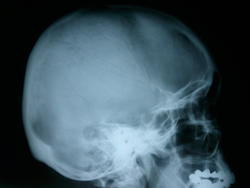

Пол пациента: Женский пол Тип патологии: Инфекция Область исследования: Череп и головной мозг Методы исследования: Rg Что это может быть? https://radiomed.ru/sites/default/files/styles/case_slider_image/public/user/134/foto0002.jpg?itok=rj0nO1qa https://radiomed.ru/sites/default/files/styles/case_slider_image/public/user/134/foto0003_001.jpg?itok=SAI4mEq1 ID:27007 Втр, 12/03/2013 - 23:00 #1 алкс Не на сайте Был на сайте: 10 лет 1 месяц назад Зарегистрирован: 24.10.2012 - 22:55 Публикации: 2915 Какая-то эндоуральная барабашка, с пластикой иль нет, но повреждение сосцевидного отростка фрезой видно. Возможно после гнойного эпитимпанита. Втр, 12/03/2013 - 23:18 #2 И.Бондаренко Не на сайте Был на сайте: 2 дня 16 часов назад Зарегистрирован: 13.09.2011 - 22:55 Публикации: 9206 Может быть ячейка сосцевидного отростка такая? Не пробовали смотреть скопически или косые снимки? Ср, 13/03/2013 - 01:29 #3 Алексей Игореви... Не на сайте Был на сайте: 6 лет 11 месяцев назад Зарегистрирован: 08.08.2012 - 21:52 Публикации: 786 По очертаниям подходит по ячейку. Вот какое происхождение секвестра внутри нее? Возможно и дефект посттраматический. "Обучая других - учишься сам". Н.И.Пирогов Ср, 13/03/2013 - 05:31 #4 ЧЮГ Не на сайте Был на сайте: 3 месяцев 2 недели назад Зарегистрирован: 31.10.2012 - 15:10 Публикации: 414 Прямая р-гр. срезана - похоже с левой стороны такая же ячейка. Ср, 13/03/2013 - 17:23 #5 Пантелеймон Не на сайте Был на сайте: 7 лет 8 месяцев назад Зарегистрирован: 16.07.2010 - 14:58 Публикации: 63 Холестеатома. А анамнез, клиника? Ср, 13/03/2013 - 17:30 #6 Фил Не на сайте Был на сайте: 6 лет 10 месяцев назад Зарегистрирован: 13.09.2011 - 16:24 Публикации: 137 А жалобы - есть ? Для холестеатомы локализация и проекция не подходящая . Ср, 13/03/2013 - 23:58 #7 brainmodel Не на сайте Был на сайте: 3 месяцев 1 неделя назад Зарегистрирован: 18.03.2010 - 22:04 Публикации: 2881 Этот "глаз" расположен кзади от углов Чителли обеих височных костей, так что ни под холестеатому, ни под фрезевое ложе не подходит. Варианты: - предоставить нормальную прямую проекцию (для начала) - прямое показание для снимков по Шюллеру и Майеру - достать пациента и выяснить анамнез, можно и прощупать интересующие области Без первых двух условий гадать можно много... Verum plus uno esse non potest.

Какая-то эндоуральная барабашка, с пластикой иль нет, но повреждение сосцевидного отростка фрезой видно. Возможно после гнойного эпитимпанита.

Может быть ячейка сосцевидного отростка такая? Не пробовали смотреть скопически или косые снимки?

По очертаниям подходит по ячейку. Вот какое происхождение секвестра внутри нее? Возможно и дефект посттраматический.

Прямая р-гр. срезана - похоже с левой стороны такая же ячейка.

Холестеатома. А анамнез, клиника?

А жалобы - есть ? Для холестеатомы локализация и проекция не подходящая .

Этот "глаз" расположен кзади от углов Чителли обеих височных костей, так что ни под холестеатому, ни под фрезевое ложе не подходит. Варианты:

- предоставить нормальную прямую проекцию (для начала)

- прямое показание для снимков по Шюллеру и Майеру